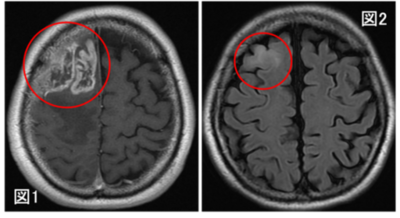

膠芽腫の画像起源の解明~いつから腫瘍は存在していたのか?~(北里大学)